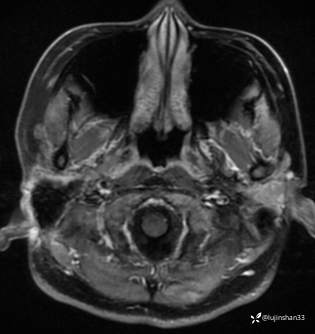

颞骨MRI:

临床诊断:1.右侧岩部胆脂瘤 2.外耳道耵聍癌术后(右)

术后MRI: